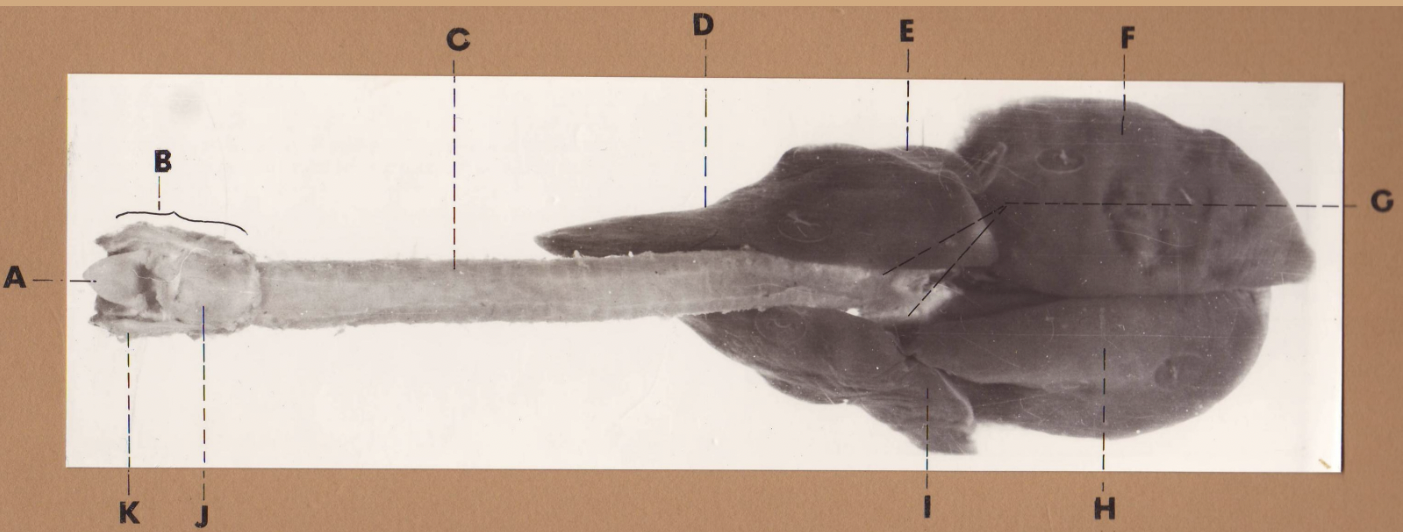

A

(cat larynx/trachea/lungs, dorsal)

epiglottis

B

(cat larynx/trachea/lungs, dorsal)

larynx

C

(cat larynx/trachea/lungs, dorsal)

trachea

D

(cat larynx/trachea/lungs, dorsal)

R cranial lobe

E

(cat larynx/trachea/lungs, dorsal)

middle lobe

F

(cat larynx/trachea/lungs, dorsal)

R caudal lobe

G

(cat larynx/trachea/lungs, dorsal)

primary bronchi

H

(cat larynx/trachea/lungs, dorsal)

L caudal lobe

I

(cat larynx/trachea/lungs, dorsal)

L cranial lobe

J

(cat larynx/trachea/lungs, dorsal)

cricoarytenoideus dorsalis m

K

(cat larynx/trachea/lungs, dorsal)

thyroid

A

(cat larynx/trachea/lungs, dorsal)

epiglottis

B

(cat larynx/trachea/lungs, dorsal)

larynx

C

(cat larynx/trachea/lungs, dorsal)

trachea

D

(cat larynx/trachea/lungs, dorsal)

R cranial lobe

E

(cat larynx/trachea/lungs, dorsal)

middle lobe

F

(cat larynx/trachea/lungs, dorsal)

R caudal lobe

G

(cat larynx/trachea/lungs, dorsal)

primary bronchi

H

(cat larynx/trachea/lungs, dorsal)

L caudal lobe

I

(cat larynx/trachea/lungs, dorsal)

L cranial lobe

J

(cat larynx/trachea/lungs, dorsal)

cricoarytenoideus dorsalis m

K

(cat larynx/trachea/lungs, dorsal)

thyroid